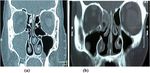

Fig. 2 CT of group B. a Pre-operative CT showing maxillary sinusitis. b Post-operative CT showing Rt ethmoid sinusitis

when comparing between related samples. Chi-square                          (8.1 ± 2.19) to (1 ± 1.2139). In group B, post-operative

(χ2) test of significance was used in order to compare                      CT finding according to the Lund and Mackey score

proportions between qualitative parameters. The confi-                      also decreased significantly from 7.3 ± 1.49 to 1.05 ±

dence interval was set to 95% and the margin of error                       1.234.